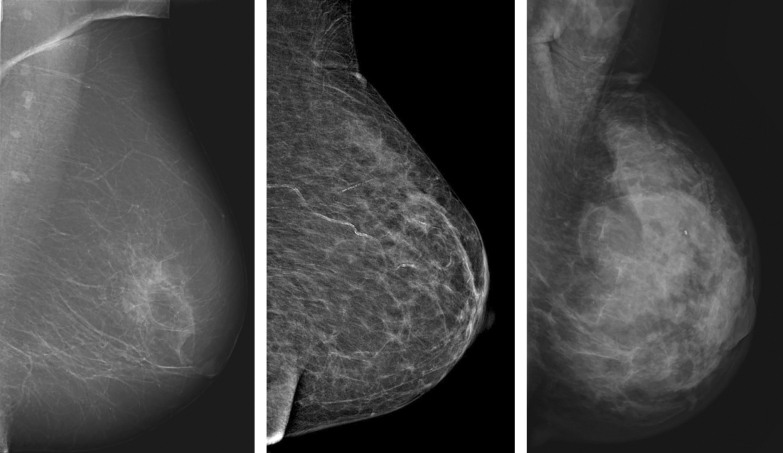

Information on the most dominant mammographic appearance of the tumour was obtained retrospectively. It should be noted that more than one appearance could have been readily visible and described in the original report, but only the most dominant appearance was recorded in the study protocol. Tumours were classified into the following comprehensive categories, based on the work by Luck et al.13: well-defined mass, partly ill-defined mass, ill-defined/diffuse mass, spiculated mass, comedo-type microcalcifications, non-specific calcifications, architectural distortion and asymmetrical density. For statistical analysis, these categories were converted into five larger categories: distinct mass (including well-defined and partly ill-defined tumours), ill-defined mass, spiculated mass, calcifications (including comedo-type and non-specific calcifications) and tissue abnormality (including the less frequent features architectural distortion and asymmetrical density). Some of the appearances are illustrated in Fig. 1.

Figure 1.

Mammographic tumour appearances. From left to right: distinct mass in the left breast of an 80-year-old woman, moderately dense breast. Spiculated mass in the right breast of 79-year-old woman, fat involuted breast. Calcifications in the left breast of a 77-year-old woman, moderately dense breast. All images acquired in the craniocaudal projection.